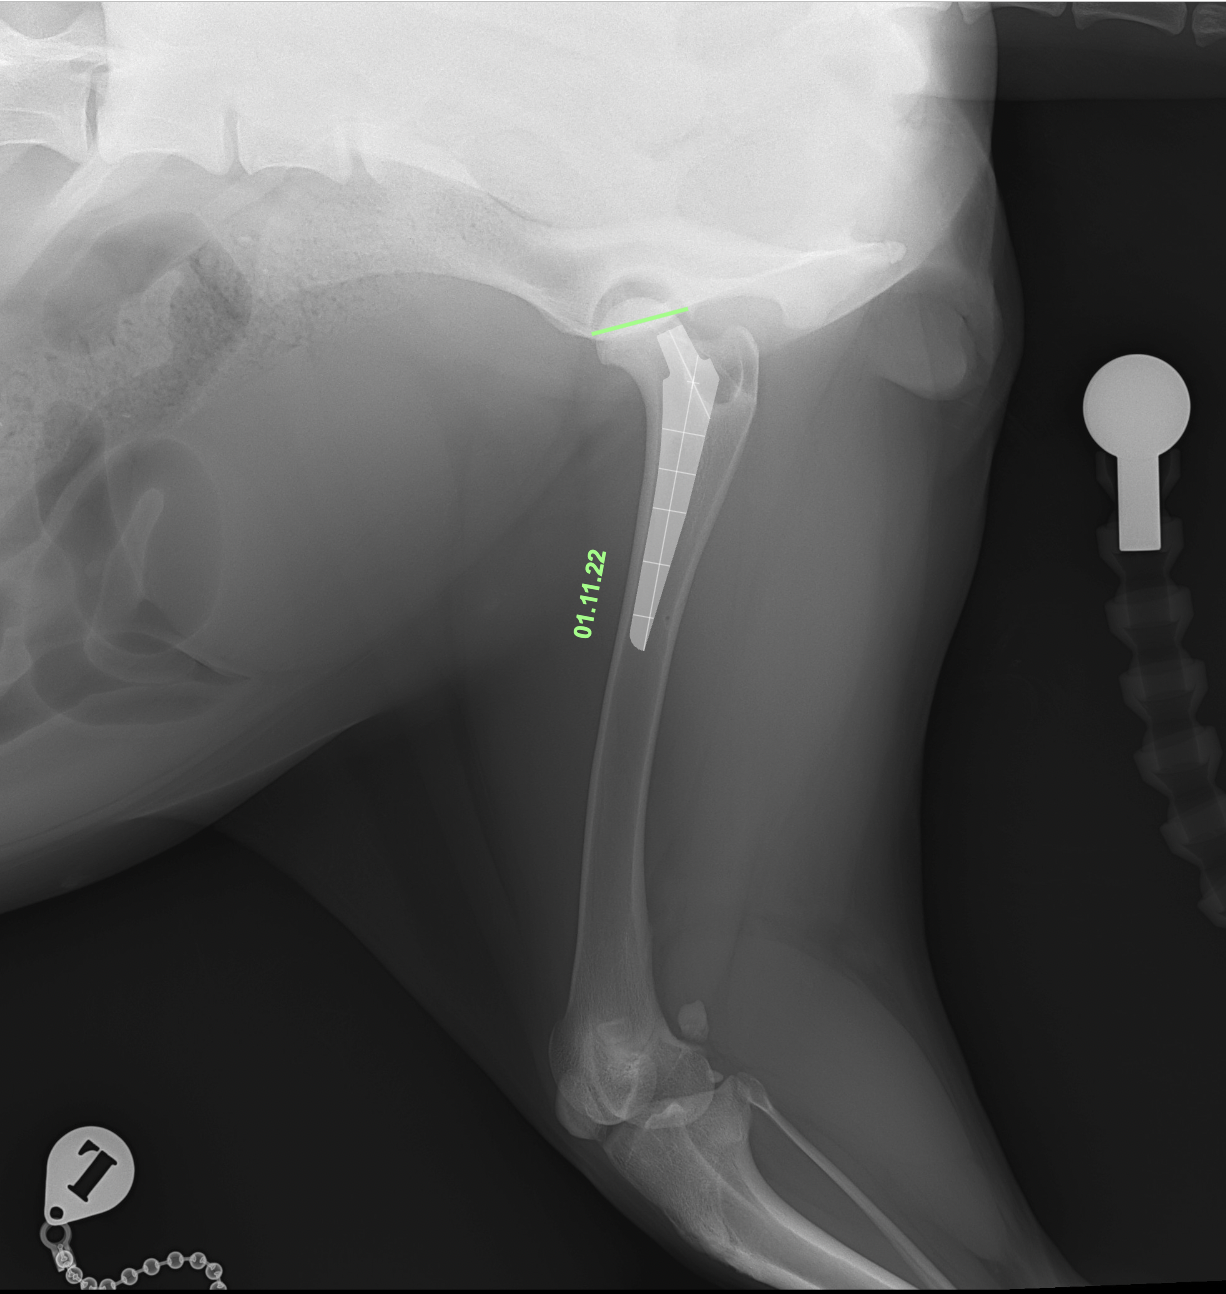

• Femoral Stem:Size M/Neck Short/Head19mm

術後X線評価ではインプラント設置は良好。

カップは寛骨臼内側壁に適切に接触し、前後柱間で良好に中心化されています。

ステムは髄腔中央に位置し、内側皮質との接触も良好です。インターロッキングスクリュー固定も適切で、安定した初期固定強度が得られています。